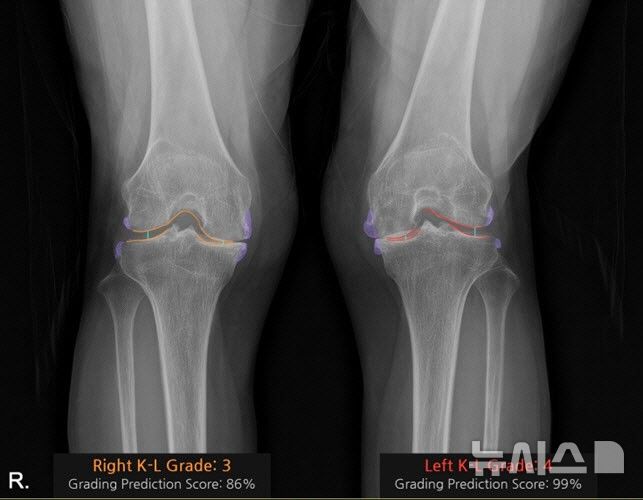

![[서울=뉴시스] 코넥티브 인공지능 관절염 판독 솔루션 '코네보 코아'(CONNEVO KOA)를 적용해 'KL 등급'(켈그렌-로렌스 등급)을 판독한 사진. 골극 변형(보라), 관절 간격(3단계 주황, 4단계 빨강)을 시각화 함. 'KL 등급'은 무릎 관절염의 진행 정도를 평가하는 데 사용되며 단계에 따라 치료 방향이 달라진다. (사진= 서울대병원 제공)](https://img1.newsis.com/2026/02/06/NISI20260206_0002057508_web.jpg?rnd=20260206095005)

[서울=뉴시스] 코넥티브 인공지능 관절염 판독 솔루션 '코네보 코아'(CONNEVO KOA)를 적용해 'KL 등급'(켈그렌-로렌스 등급)을 판독한 사진. 골극 변형(보라), 관절 간격(3단계 주황, 4단계 빨강)을 시각화 함. 'KL 등급'은 무릎 관절염의 진행 정도를 평가하는 데 사용되며 단계에 따라 치료 방향이 달라진다. (사진= 서울대병원 제공)